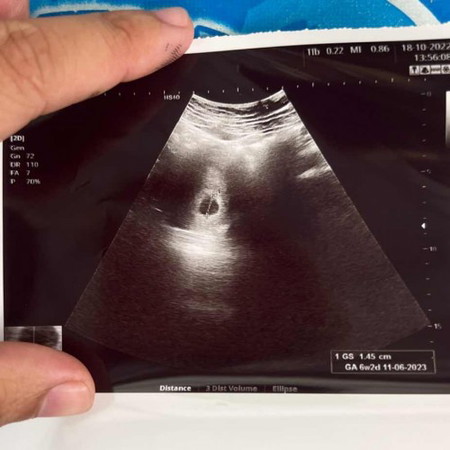

บ้านนี้ซาวตอน 6 สัปดาห์ 2 วัน แบบนี้ปกติไหมค่ะ ซาวผ่านหน้าท้องค่ะ กังวลใจอยู่พอสมควร อยากเจอนางบ้าง